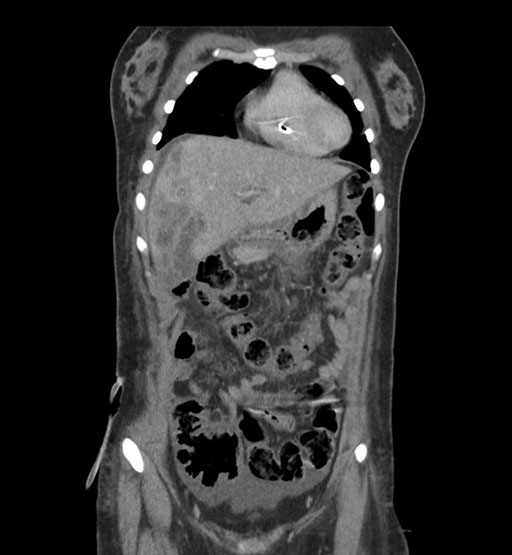

Coronal Arterial